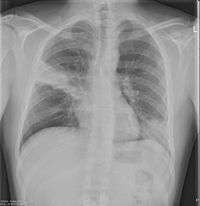

Chest X-rays and X-ray computed tomography (CT) can reveal areas of opacity (seen as white), indicating consolidation. CAP does not always appear on x-rays, because the disease is in its initial stages or involves a part of the lung an x-ray does not see well. In some cases, chest CT can reveal pneumonia not seen on x-rays. X-rays can often mislead, as Heart failure or other types of lung damage can mimic CAP on x-rays.[12]

Chest X-rays of a CAP patient before (left) and after treatment